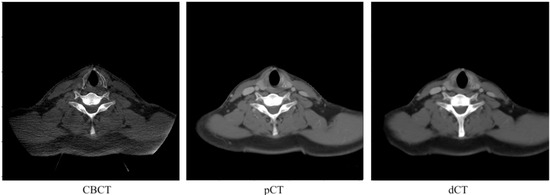

3.2. Image Quality Evaluation in Preserving Anatomy